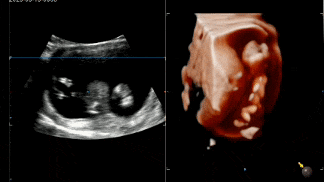

各种状态的宝贝

趴着的

害羞的

侧躺

倒立

举手

有坐着不爱动的

还有扭来扭去不老实的

甚至能在肚子里练“功夫”

出其不意的一拳,动作快的都看不清ta的招式

悠闲自得

吃着手指还翘着二郎腿

在妈妈的肚子里荡啊荡~